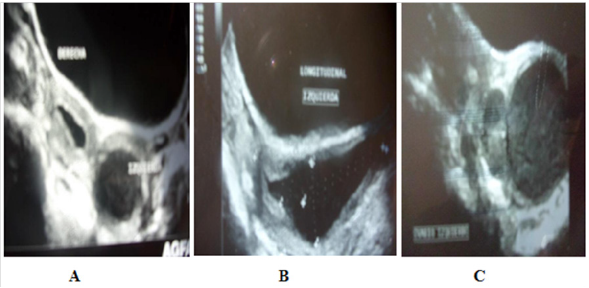

El primer caso corresponde a adolescente de 10 años y 5 meses de edad, quien es referida de pediatría para evaluación ginecológica por presentar tumoración quística gigante (180 cc aprox.) para uterina derecha en evaluación ecográfica pélvica previa, asociada a dolor pélvico tipo cólico hipogástrico de fuerte intensidad de 3 meses de evolución y resultados de marcadores tumorales Ca 125; Ca 19,9; α feto proteína; CEA y Subunidad β de HcG normales, al examen físico se observan mamas y distribución de vello pubiano III (S3/P3 según escala madurativa de Marshall y Tanner); abdomen blando, deprimible y doloroso a la palpación profunda debido a tumoración visible en hipogastrio y fosa iliaca derecha con genitales externos de aspecto y configuración normal e himen intacto, encontrándose al tacto bimanual (abdomino rectal) tumoración palpable renitente dolorosa correspondiente a cilindro útero vaginal distendido; se realiza ecografía pélvica transabdominal que revela presencia de dos úteros ambos con endometrio en su interior en proyección transversa se observa imagen quística retrovesical y ovario derecho con morfología normal; al rotar el transductor en proyección sagital se evidencia una imagen quística (89 cc) que se continua con cuerpo uterino derecho correspondiéndose esta con segmento vaginal derecho distendido (hematocolpos) y ovario izquierdo normal además de agenesia renal derecha y riñón izquierdo de morfología normal ( Fig. 2).

El segundo caso correspondió a adolescente de 12 años 2 meses proveniente del estado Aragua; con antecedentes de menarca a los 11 años 6 meses, ciclos regulares y patrón 5/28-30 dismenorreicos, con aumento progresivo en intensidad del dolor descrito y poca respuesta a la toma de AINES por vía oral, quien amerito hospitalización por abdomen agudo quirúrgico seis meses previos a la consulta, encontrándose a la laparotomía exploradora: útero doble, adherencias laxas en abdomen y pelvis, abundante contenido hemopurulento y piosalpinx izquierdo. Ameritando liberación de adherencias, aspiración del contenido abdominal y pélvico y salpingostomia izquierda; además drenaje por punción vía vaginal de contenido hemático oscuro y fétido; con evolución satisfactoria en postoperatorio de quince días con triple cobertura de antibióticos; siendo referida del servicio de cirugía pediátrica para evaluación ginecológica infanto juvenil; encontrándose mamas y distribución de vello pubiano estadio IV (S4/V4); abdomen blando no doloroso a la palpación profunda en hipogastrio y ambas fosas iliacas sin tumoraciones visibles; en genitales se observa doble introito vaginal separado por tabique vaginal longitudinal grueso y completo confirmado tras realizar la prueba del hisopo con azul de metileno reportando una vaginometria de 7 cm del lado izquierdo; a la ecografía pélvica se confirma útero didelfo con hematómetra izquierdo (proyección transversa) e imagen quística en la parte alta de hemivagina izquierda compatible hematocolpos por vagina septada izquierda (proyección sagital) (Fig. 3); a la ecografía abdominal con énfasis renal se confirma ausencia de riñón izquierdo con riñón derecho normal estableciéndose el diagnóstico de Síndrome de OHVIRA.

A las pacientes se les realizaron además de ecografía pélvica, estudios complementarios como RMN y TAC de abdomen y pelvis con contraste, (dos casos); con el fin de establecer las referencias anatómicas de los órganos por contigüidad y la permeabilidad o no de ambos hemisistemas- Por la asociación con alteraciones renales se realizaron otros estudios como: gammagrama renal con DMSA, la cistografía miccional retrograda y / o urografía de eliminación (Fig. 4).